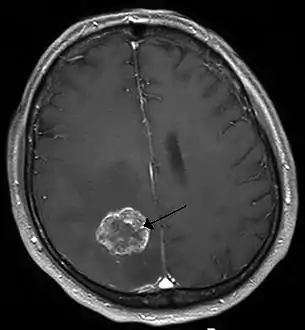

Brain imaging (neuroimaging such as CT or MRI) is needed to determine the presence of brain metastases.[5] In particular, contrast-enhanced MRI is the best method of diagnosing brain metastases, though detection is primarily done by CT.[9] Biopsy is often recommended to confirm diagnosis.[5]